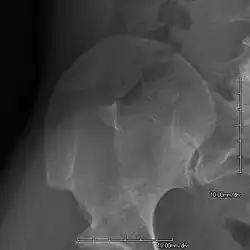

AP radiograph of the right iliac crest showing a bony exostosis or posterior iliac horn, which is pathognomonic of NPS

• Exostoses arising from the posterior aspect of the iliac bones ("iliac horns") are present in as many as 70-75% of patients; this finding is considered pathognomonic for the syndrome.